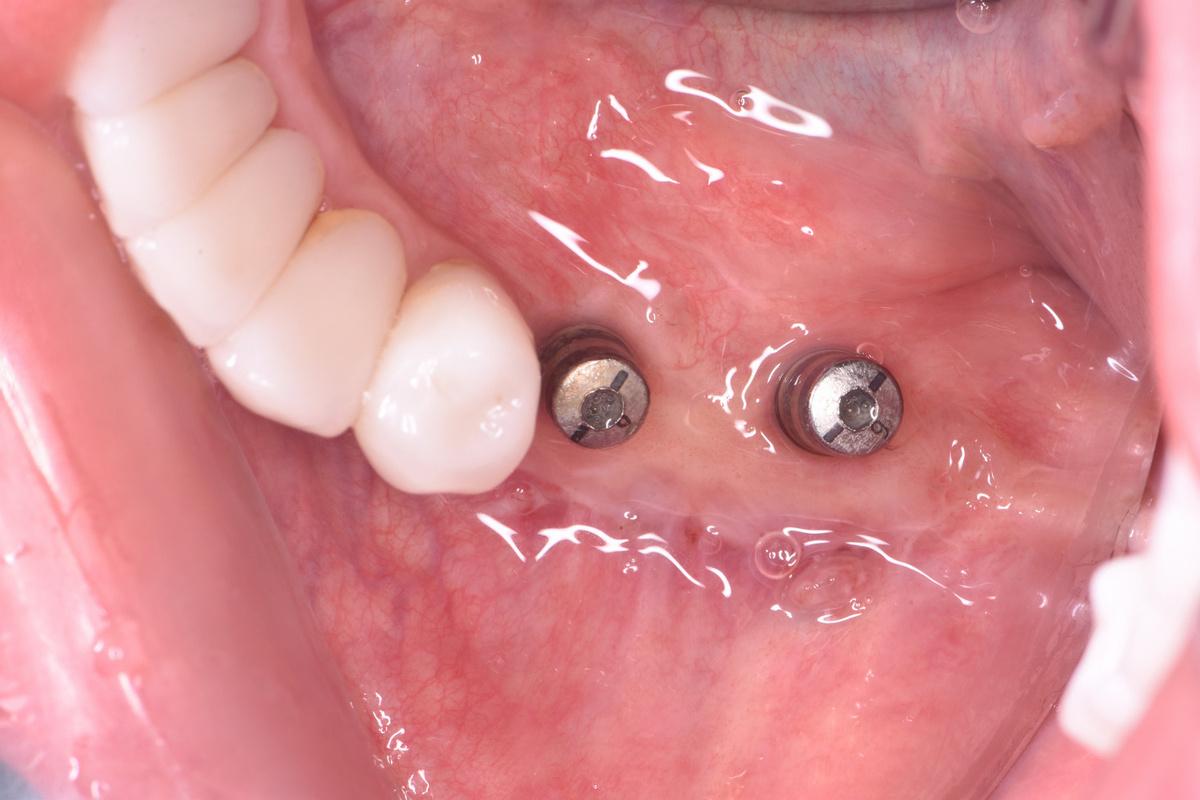

Имплантация

Через 6,5 месяцев после двустороннего синус-лифтинга проводим имплантацию на верхней челюсти. За 1 операционный день устанавливаем 6 имплантатов «Dentium» — 3 слева и 3 справа

Операция длилась 4 часа, проводилась в седации

Ещё через 2 месяца — установка формирователей и мягкотканная пластика для формирования массива кератинизированной десны в области имплантации

Операция по установке формирователей и пластика длилась 2 часа, проводилась в седации

Следующий этап — имплантация на нижней челюсти справа. Через 6 месяцев после остеопластики с использованием костных блоков

Операция длилась 2 часа, проводилась в седации

Также через 2 месяца устанавливаем формирователи десны и проводим пластику мягких тканей с использованием соединительнотканного трансплантата

И, наконец, последний хирургический этап — установка 2 имплантатов в 3-ем сегменте слева. В данной области, где дефицит кости был самым катастрофическим, остеоинтеграция заняла 12 месяцев ️ Результат через месяц после установки формирователей и процедуры обязательного восстановления мягких тканей: